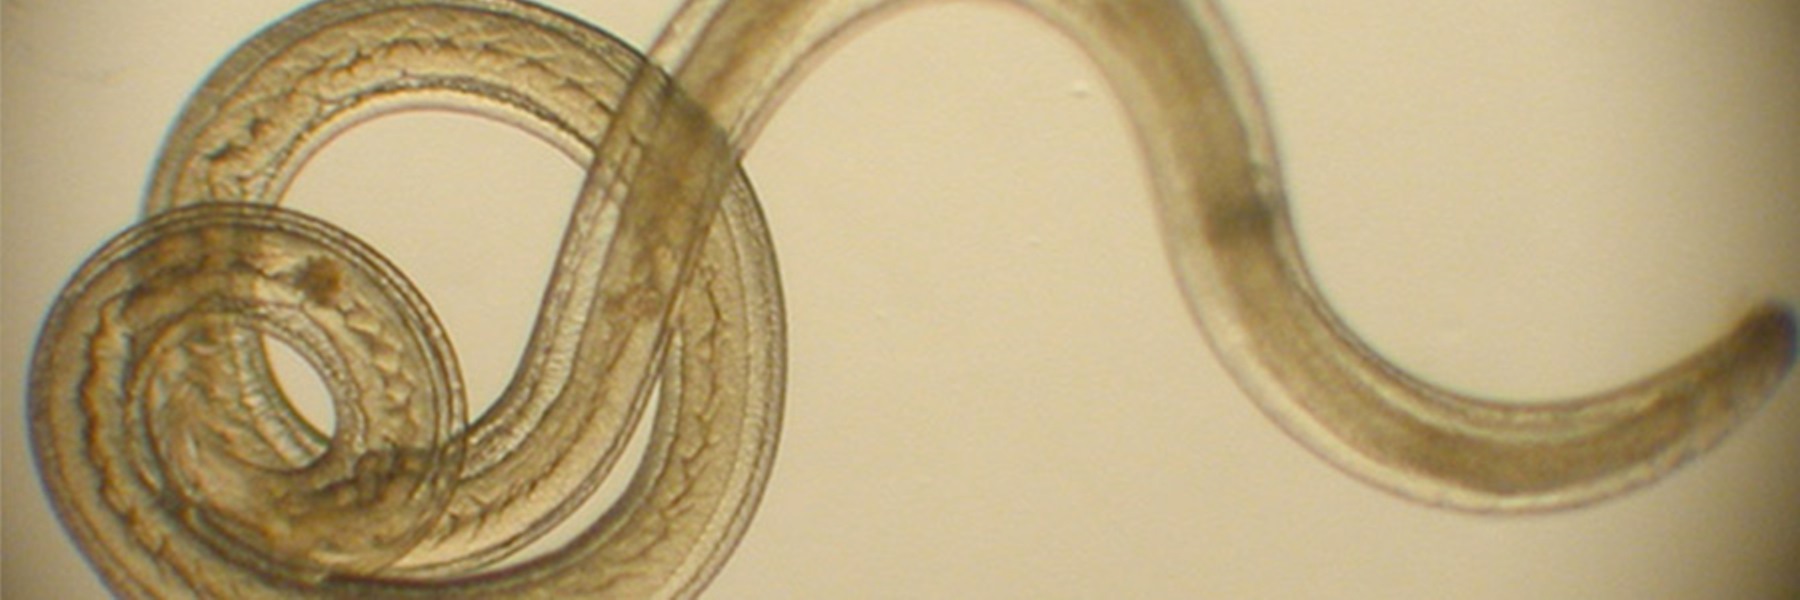

Микрофотографии яиц гельминтов Toxocara canis

Раздел: Фотоэссе